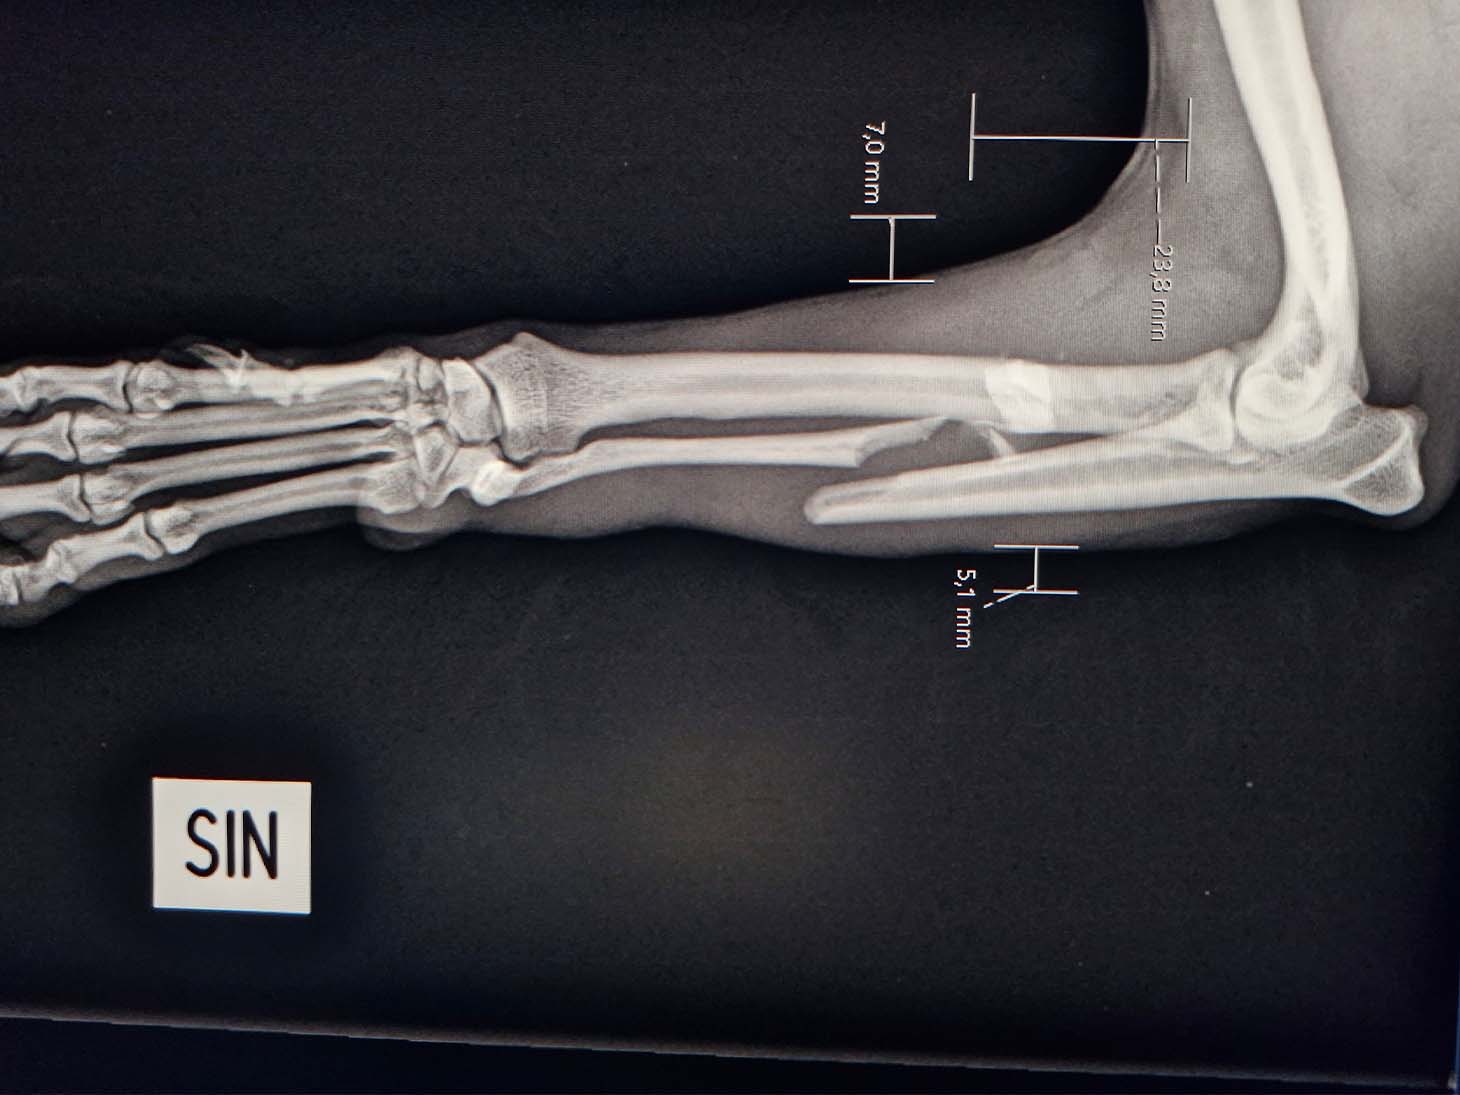

In April 2025, a 3-year-old, 5.6 kg mixed breed dog suffered a severe injury after being struck by a bicycle. The patient presented with a complex proximal comminuted radius fracture and a mid-diaphysis ulnar fracture, classified as an open fracture Grade 1. Thanks to swift surgical intervention and advanced technology, the dog is now back to its energetic self.

- The severely comminuted radius fracture was stabilized using a 2.0 mm titanium LeiLOX plate, specifically chosen to manage the comminution in combination with a supportive repair of the ulna.

- The ulna fracture was addressed with our innovative 1.0 mm titanium LeiLOX plate, secured by 1.3 mm locking screws. This combination provided robust, yet minimally disruptive, fixation crucial for a small patient. The surgical site was thoroughly flushed, and the patient received Cefazolin both perioperatively and for three days post-op to manage the open wound.